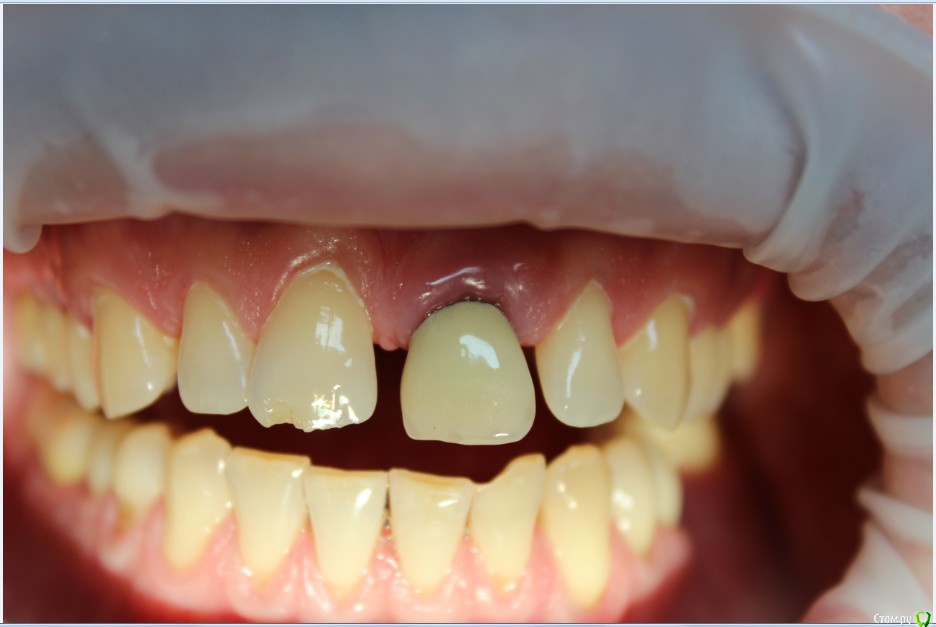

Рустам Опубликовано 20 июля, 2015 Поделиться Опубликовано 20 июля, 2015 Здравствуйте коллеги! Подскажите по клиническому случаю пожалуйста. Обратился пациент в клинику с подвижной коронкой на зубе 2.1, на рентгене диагностирован перелом корня, планируем удаление с одномоментной имплантацией и желательно с немедленной нагрузкой. Система имплантатов "Osstem", на этой системе я ранее не протезировал (работал с "Mis" и "Super Line") и вообще ранее немедленно не нагружал имплантаты. Хирург назначил удаление и иплантацию на 23.07, я смогу принять пациента только 24.07 утром, необходимо заказать временный абатмент, подскажите какой именно из каталога нужно заказать?Имплантолог заказал два имплантата Osstem TSIII SA диаметром 4,0 и 4,5.Я планирую делать временную прямым способом по ключу снятому со старой коронки во рту. Может лучше через оттиск заказать лабораторную временную?P.S. пациента эстетически все устраивало, ортодонтию не хочет. Ссылка на комментарий